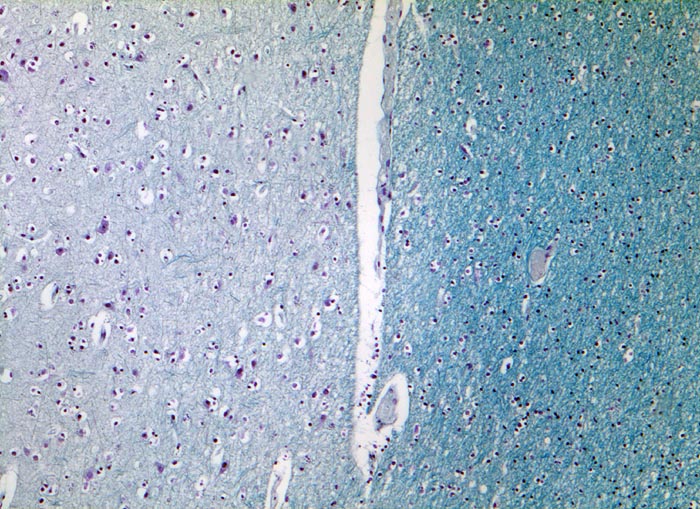

• Alter, scharf begrenzter Entmarkungsherd mit Verlust der blauen Myelinscheiden in der Holmes Luxol Färbung.

• Vollständiger Verlust der Markscheiden (fehlende blaue Farbe) bei erhaltenen Axonen (schwarze Fasern).

• Vereinzelte vorwiegend perivaskulär lokalisierte mononukleäre Entzündungszellen und mit Myelinbruchstücken beladene Makrophagen.